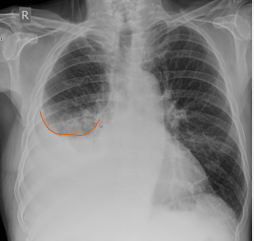

What does this CXR indicate? - Pneumoperitoneum - Pneumothorax - Pulmonary oedema - Consolidation - Pleural effusion

What does this CXR indicate? - Pneumoperitoneum - **Pneumothorax** - Pulmonary oedema - Consolidation - Pleural effusion